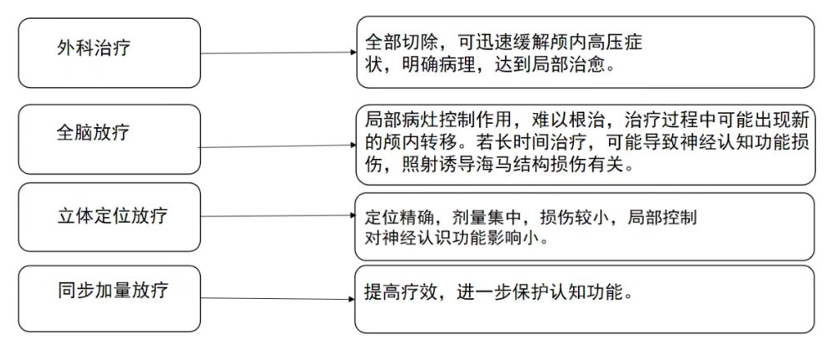

电子烟会引起肺癌吗?

电子烟会引起肺癌吗?

电子烟患肺癌的风险更小?

电子烟患肺癌的风险更小?

华西专家说,每抽一口电子烟,你可能离癌症、呼吸系统疾病更近一点点...

华西专家说,每抽一口电子烟,你可能离癌症、呼吸系统疾病更近一点点...